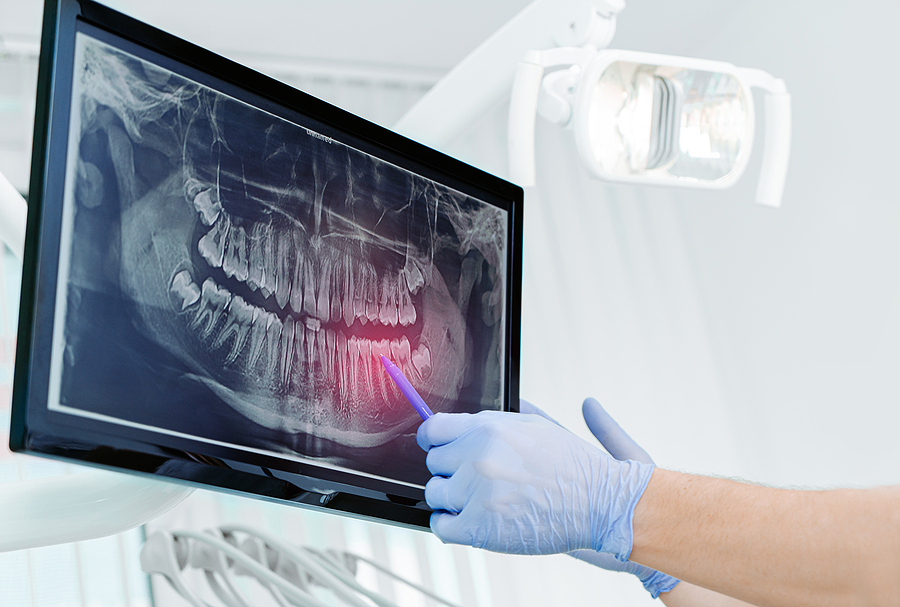

Traditional X-rays use a form of radiation to capture images of your teeth and oral structures, but the process can be time-consuming. They also expose you to more radiation than necessary. With digital X-rays, our dentist can capture images immediately using a small sensor placed in your mouth. This sensor is attached to a computer screen that allows us to view the images instantly.

The images are more precise and can also be sent electronically for further diagnosis or treatment. Our dentist can review the images with you and discuss any necessary procedures.

The digital images help our dentist identify problem areas in the mouth that wouldn’t be as visible during a visual exam or when using traditional X-rays. For example, the small sensor that captures these images can help the dentist see cavities between teeth. In addition, our dentist can adjust the images to help highlight specific areas of the mouth.